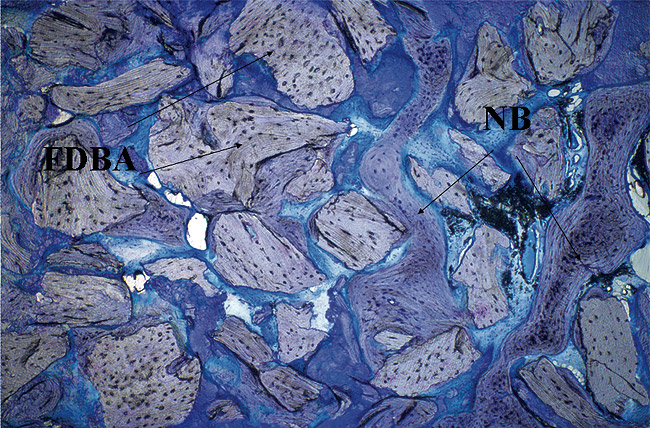

A 51-year-old man presented with a 12-mm probing depth on the mesiobuccal and distalbuccal surfaces secondary to a root fracture extending to the apex of the maxillary left canine (Figure 14 ). The tooth was extracted without flap elevation, and the socket and periradicular defect were thoroughly degranulated using magnification and fiber optic illumination. The socket and bony defect were grafted with an FDBA wetted with rhPDGF-BB (10 minutes). A resorbable collagen membrane was cut, adapted, and stabilized with cyanoacrylate over the extraction socket, as in the Bio-Col technique.44 Healing proceeded uneventfully with clinical closure and epithelialization of the extraction site after 21 days. At 5 months post-treatment, the radiographic findings were consistent with complete bone fill of the defect (Figure 15 ). The osteotomy for implant placement was prepared with a trephine bur. The core specimen was submitted for histologic evaluation; the findings revealed areas of intense osteogenesis with new bone trabeculae surrounding and interconnecting the graft particles (Figure 16 ). Histologic evidence showed new bone repopulating regions of graft particles (Figure 17).

Figure 16  Photomicrograph demonstrating areas of intense osteogenesis with new bone trabeculae surrounding and interconnecting the graft particles. Original magnification X5; toluidine blue stain.

Figure 16

Figure 17  Photomicrograph showing evidence (*) of new bone repopulating a region of a graft particle. Original magnification X 10; toluidine blue stain.

Figure 17